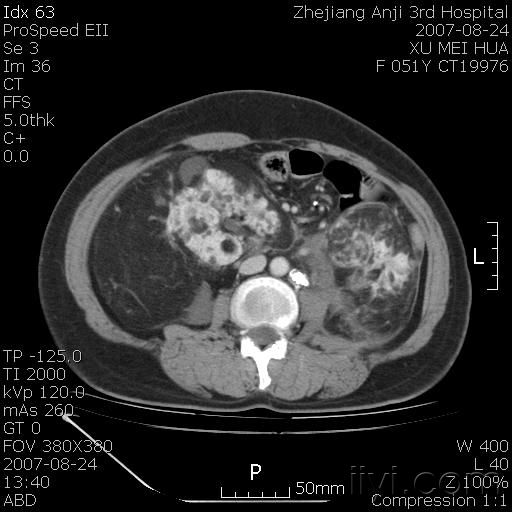

以下是引用还珠格格在2007-8-27 10:19:00的发言:[br]双侧肾脏形态失常,可见巨大的以低密度脂肪为主的混合性肿块,占据中下腹,残留的肾组织轻度强化,增强后肿块内实质部分呈峰窝状强化,低密度区无强化。另左侧肾盂轻度积水。根据病史 考虑 双肾血管平滑肌脂肪瘤可能性大。[br] 鉴别诊断 1、脂肪瘤,境界清楚,肿块内完全是脂肪,几乎没有软组织成分; 2、畸胎瘤:罕见,除有软组织成分外,另一特征是有钙化或骨化影组织。